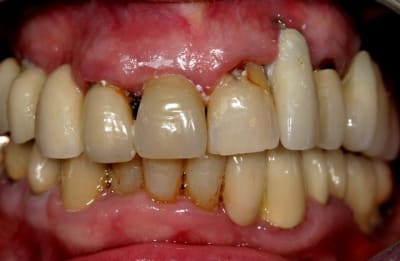

oui ce sont des provisoire avec armature....ils sont meulés car l'occlusion ct pas ça...

Moi je prends la patiente en l'état...perso je pense que les bridges dento-implanto porté sont à reserver dans les cas ou on a vraiment pas le choix.

Le conjonctif sur la 22...je vois pas comment ça pourrait prendre je vois presques des spires de l'implant...

Merci de ton analyse que je partage grandement...

Effectivement c'est du grand n'importe quoi, et j'aime pas ce genre de situtation on la patiente sent bien qu'il y a un truc pas top avec l'autre praticien et aimerais bien qu'on lui dise que c'est pas terrible ce qu'on lui a fait...